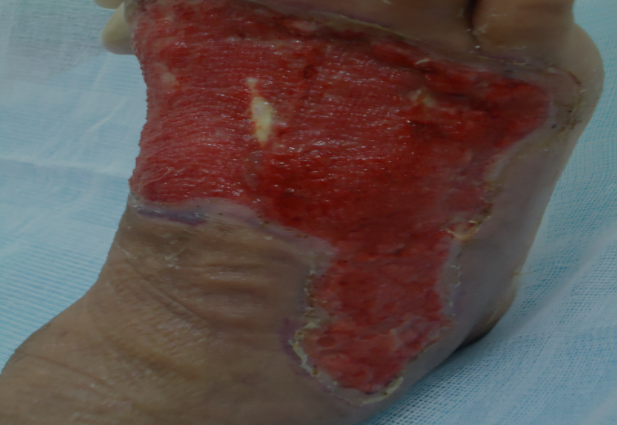

Chegando lá, deparou-se com muitos pacientes que eram portadores de lesões ulceradas crônicas nos membros inferiores, as Ulceras Varicosas.

Após os problemas políticos aos quais mencionamos ao ir clinicar em Minas Gerais encontrou o que faltava: Muitos pacientes com o problema e muito conhecimento popular que somado aos conhecimentos científicos que tinha chegou-se a uma conduta que podemos chamar de CONDUTA ÚNICA, para o tratamento destas lesões, que independente do tratamento ou tratamentos já realizados e o tempo do inicio das lesões. O tratamento realizado com esta CONDUTA ÚNICA em apenas 15 ou 30 dias, cura-se as lesões Varicosas “pele-a-pele”. Mesmo pacientes com fatores complicativos como o caso de “Pés Diabéticos”.

ANTES E DEPOIS

Confira os resultados reais de nossos pacientes